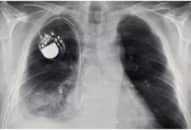

Người đàn ông 34 tuổi ở Vĩnh Long nhập viện trong tình trạng hôn mê sâu, với vết thương ở vùng ngực bị đâm bằng kéo gây thủng tim, mất nhiều máu.